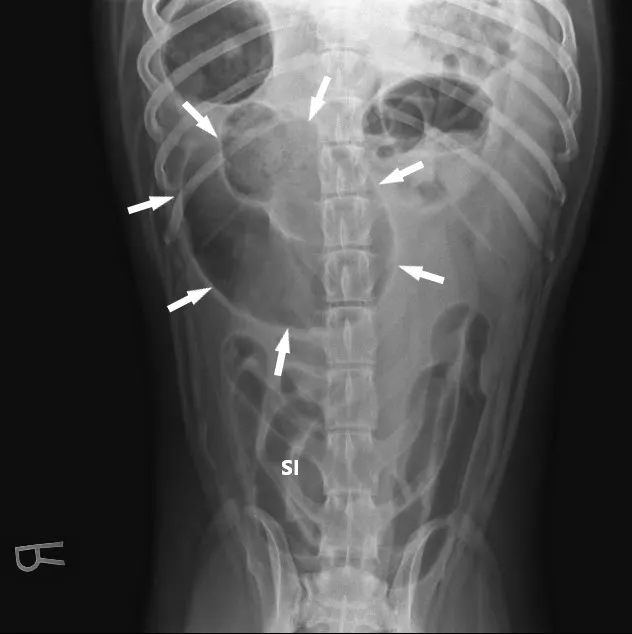

A lubricated 10 French red rubber catheter was inserted rectally and connected to a 60-mL catheter-tip syringe. Air (2 mL/kg) was injected while the anus was occluded by pinching off the anal tissue. Additional 3-view abdominal radiographs revealed normal-diameter, gas-filled small intestines; a markedly gas-distended proximal colon; soft-tissue opacity abnormally located in the right cranial abdomen; and narrowing of the distal lumen of the descending colon (Figure 2). The remainder of the radiographs were unremarkable. Radiographs were assessed by multiple board-certified radiologists, and there was a high index of suspicion for colonic torsion.

FIGURE 1A

Right lateral (A), left lateral (B), and ventrodorsal (C) abdominal radiographs demonstrating marked dilation of a single bowel loop with gas and amorphous material in the right cranial abdomen, suspected to be the colon (arrows). Caudal displacement of the small intestines (SI) can also be seen. The descending colon (Co) is poorly visualized.